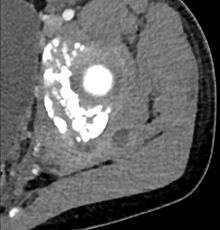

| Transverse T2 magnetic resonance imaging section through the hip region showing abscess collection in a patient with pyomyositis. | |